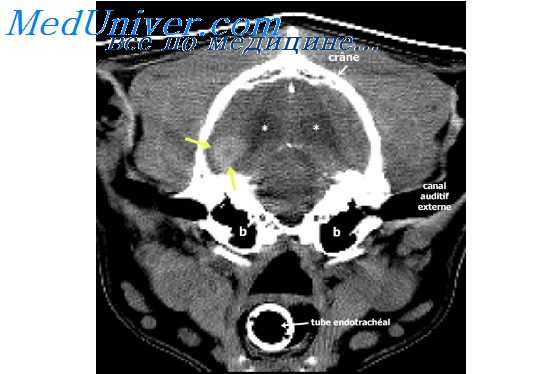

- Перед проведением миелографии больному с симптомами повышенного ВЧД или с распространенными метастазами необходимо исключить наличие внутричерепных метастазов.